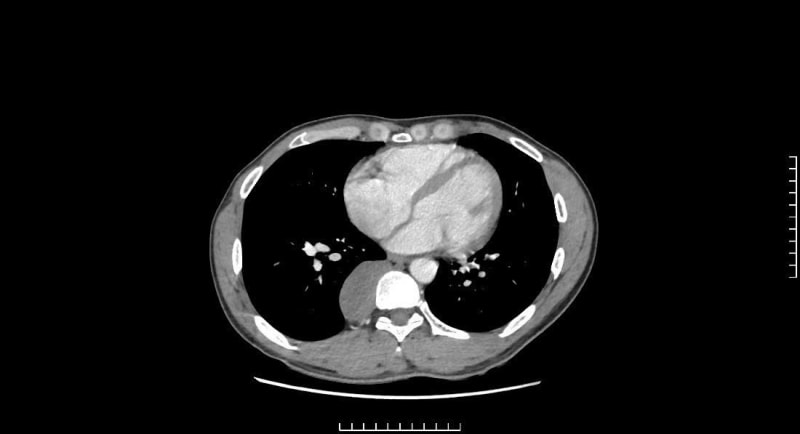

Tại bệnh viện, nam thanh niên được bác sĩ tiến hành thăm khám lâm sàng và thực hiện các xét nghiệm thăm dò chuyên sâu. Kết quả chụp CTscanner và MRI lồng ngực phát hiện khối u kích thước lớn (33x90x32mm) nằm sát cột sống D7 - D11. Sau khi hội chẩn, các bác sĩ chẩn đoán bệnh nhân bị bệnh lý u trung thất sau, theo dõi u thần kinh và chỉ định phẫu thuật nội soi lồng ngực.

Từ kết quả chụp CTscanner và MRI lồng ngực trên người bệnh cho thấy, khối u kích thước lớn nằm sát cột sống D7 - D11. Qua hội chẩn, các bác sĩ chẩn đoán bệnh nhân bị bệnh lý u trung thất sau, theo dõi u thần kinh và chỉ định phẫu thuật nội soi lồng ngực.